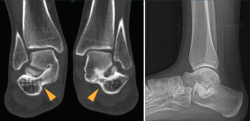

Figura 4. EpiFlex®. Matriz de colágeno acelular humano.

La técnica realizada en nuestros casos fue la resección del puente calcaneoastragalino y la interposición de matriz dérmica de colágeno humano acelular, de marca EpiFlex®(Figura 4), reducción del pie plano valgo y artrorrisis mediante endoprótesis de tipo PitStop®(Figura 5).